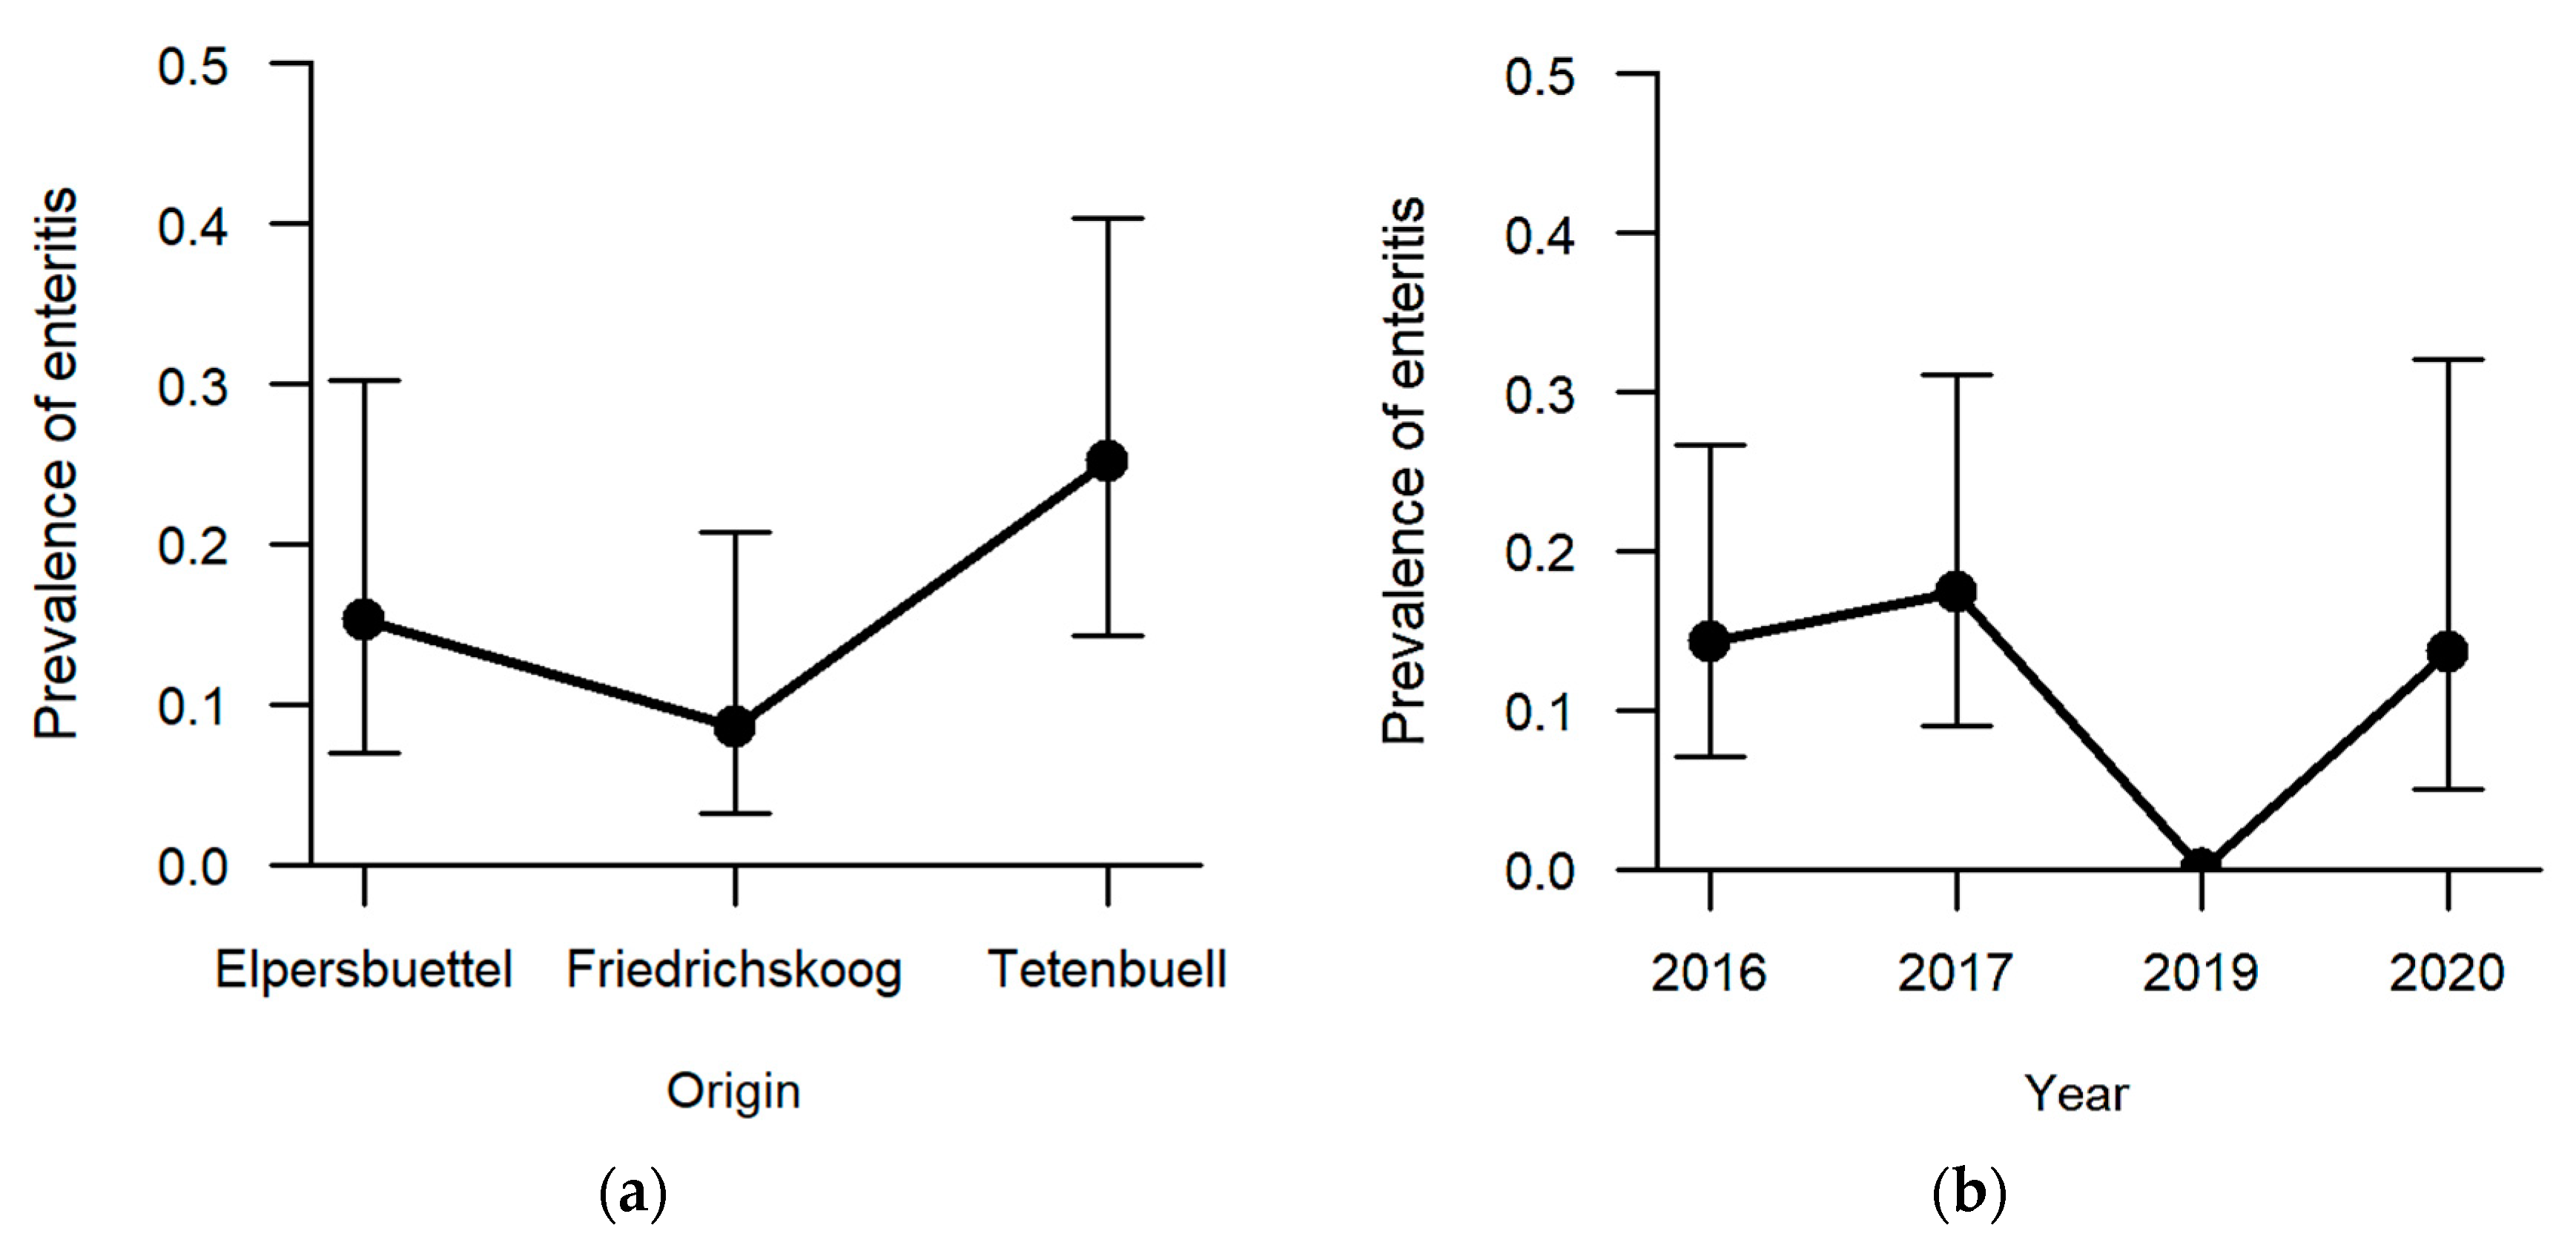

Enteritis was one of the less frequent findings (13.5%, n = 21) with regard to the six explicitly analysed pathomorphological findings. The occurrence of enteritis was not significantly affected by sex and age category. Regarding the hunting grounds, enteritis was diagnosed the most in hares sampled in Tetenbüll (21.2%, n = 11), followed by those from Elpersbüttel (12.5%, n = 6) and Friedrichskoog (7.3%, n = 4). The predictor hunting ground was retained in the model selection process based on AICc, and a

p-value of 0.097 was obtained in likelihood ratio tests, so that we can neither rule out nor confirm an effect of hunting ground on the prevalence of enteritis (

Figure 7a). On the other hand, a significant effect was observed between sampling years (

p = 0.027;

Table S1). Whereas inflammation of the intestine was not observed in 2019, at least 15% of the sampled individuals suffered from enteritis in the remaining sampling years (2016: 15.1%, n = 8; 2017: 18.8%, n = 9; 2020: 14.8%, n = 4) (

Figure 7b).

78]. Another reason might be the high prevalence of enteritis in hares from Tetenbüll, with almost one-quarter of sampled hares affected. A definite cause for the enteritis cases was not identified. Interestingly, this pathomorphological finding was not diagnosed in 2019, while in the same year, the proportion of juveniles increased. A simultaneously conducted study on deceased hares in this federal state also reported less cases of enteritis in 2019 compared to other study years [

43]. Particularly due to less precipitation and higher temperatures in some years, the usually high parasitic pressure can be decreased [

71,

79], and thus possibly also the prevalence of enteritis, which can be caused by high infection levels of parasites [

61,

62,

66,

80]. In 2019, the summer was very dry and hot [

81]. However, when merging pathomorphological and parasitological data, almost every hare examined in our study was proven to excrete parasite eggs or oocysts (96.1%). A high intensity of parasitic infections in